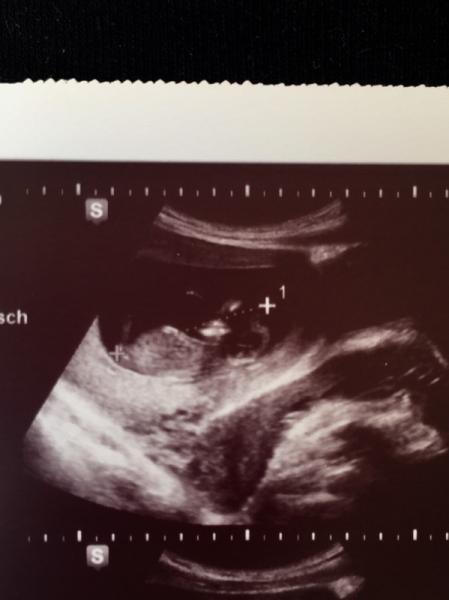

Hallo Mädels, Wie schon in der Überschrift hatte ich jetzt meinen 2 fa Termin + erstsemesterscreening und trotzdem keine vaginsle Untersuchung weder beim ersten Termin 8ssw noch jetzt. Ich kenne das nicht aus der ersten ss. Gibts noch jmd ohne v Untersuchung ? Im mutterpass steht übrigens in der Spalte vaginale Untersuchung : O.B also ohne Befund... Lg Tambelia

Also bei mir wurden beide Ultraschalluntersuchungen vaginal gemacht und heute hat meine Frauenärztin auch abgetastet und den Gebärmutterstand eingetragen. Dafür hatte ich quasi kein wirkliches Erstsemesterscreening. Sie hat nur eine Minute geschaut und gut. Ich denke wenn du keine Blutungen hast ist die vaginale Untersuchung noch nicht so relevant.